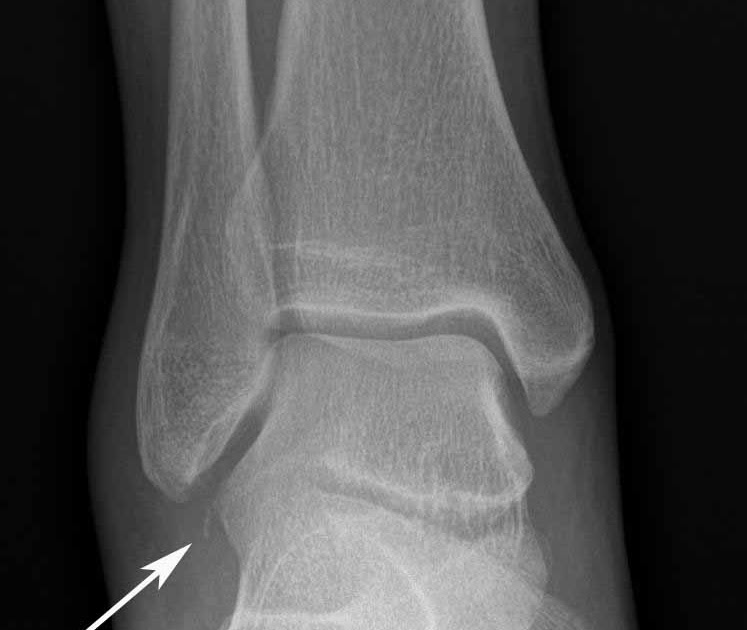

From footeducation.com

Lateral Talar Process Fractures FootEducation Talus Bone Injury The talus is the bone that makes up the lower part of the ankle joint. It can cause significant swelling and bruising. An unstable talus fracture occurs when a piece of bone is displaced from its attachment. A talus fracture is a painful break of one of the major bones of the ankle. A badly twisted ankle can also cause. Talus Bone Injury.

From radiologyinthai.blogspot.com

RiT radiology Fracture of the Lateral Process of Talus Talus Bone Injury It is between your shin bone (tibia) and heel bone (calcaneus). The talus is a bone in your foot that helps make up the ankle joint. Common causes include motor vehicle collisions, falls from a significant height, and Injuries that could cause a talus fracture include a fall from a great height or a car accident. You have broken the. Talus Bone Injury.

From sites.uw.edu

Hawkins Classification of Talar Fractures UW Emergency Radiology Talus Bone Injury A talus fracture is a painful break of one of the major bones of the ankle. An unstable talus fracture occurs when a piece of bone is displaced from its attachment. Talus fracture is a painful condition where the talus, an important bone that connects the foot and ankle, is broken. Injuries that could cause a talus fracture include a. Talus Bone Injury.

From radiopaedia.org

Anterior talofibular ligament injury with an avulsed bone fragment from Talus Bone Injury A talus fracture is a painful break of one of the major bones of the ankle. The talus is the bone that makes up the lower part of the ankle joint. Because the talus is so important for ankle. An unstable talus fracture occurs when a piece of bone is displaced from its attachment. Talus fracture is a painful condition. Talus Bone Injury.